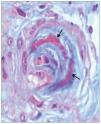

El tratamiento hipotensor consiguió controlar óptimamente la PA. De modo paralelo se normalizó la cifra de plaquetas y desaparecieron los signos de hemólisis. Tras ello se practicó una biopsia renal percutánea, que evidenció como signo más llamativo una afectación difusa y grave de las arteriolas renales, mostrando lesiones de endarteritis proliferativa (figura 2) y estrechamiento de las luces junto con lesiones de necrosis fibrinoide en la pared (figura 3). Los glomérulos presentaban cambios isquémicos sin presencia de trombos en la luz de los capilares. Se detectaban signos de discreta nefritis tubulointersticial. La inmunofluorescencia era negativa.

Figura 3. Arteriola renal con lesiones de necrosis fibrinoide en la pared (flechas). Tinción de tricrómico de Masson (magnificación ×20).